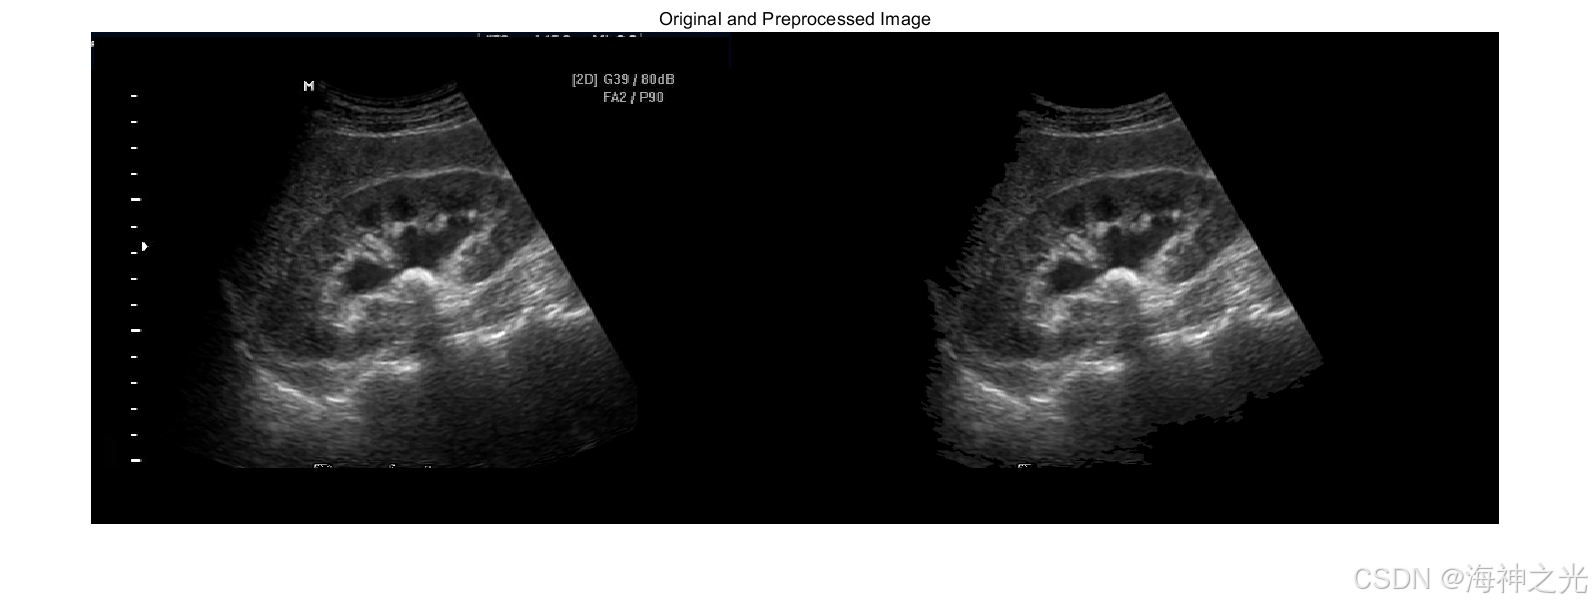

⛄三、运行结果